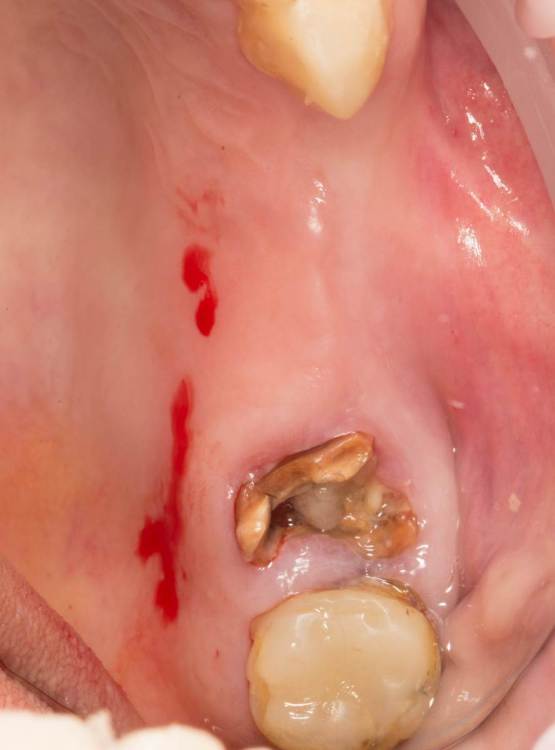

Женька Опубликовано 24 июля, 2023 Поделиться Опубликовано 24 июля, 2023 Тема ради одной фотки конечно, но всё-таки вопрос есть. Говорят МСТ профайлер не задевает стенки имплантата. Кмк, всё-таки задевает. Или всё-таки кажется? По кейсу: 2 имплантата, оба по шаблону. Черт дёрнул пройти глубже чем планировал в 1.6, фрезой перфо не создал, но кортикалку в ноль убрал. И при отслойке всё-таки порвал немного. Тампонировал губками, пробы отрицательные. Вроде нигде не перемудрил в этот раз, @АнтонТЛТ ? 3 Ссылка на комментарий

Raystom Опубликовано 24 июля, 2023 Поделиться Опубликовано 24 июля, 2023 @Женькакажется. Там юбка направляющего пина не даёт портить стенки. Ссылка на комментарий

Женька Опубликовано 24 июля, 2023 Автор Поделиться Опубликовано 24 июля, 2023 @Raystom я про эти участки Ссылка на комментарий

Raystom Опубликовано 24 июля, 2023 Поделиться Опубликовано 24 июля, 2023 @Женька хотя да, если присмотреться, то есть небольшое снятие фаски шейки по внутреннему контуру. Ссылка на комментарий